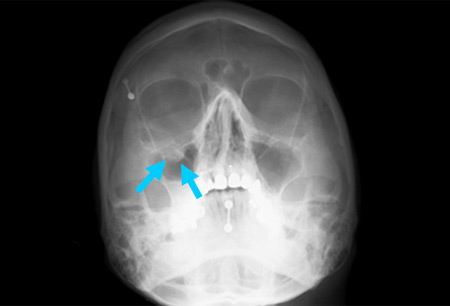

Right orbital blow-out fracture; teardrop sign on occipitomental 15° x-ray

From the personal collection of Dr Alistair Cobb